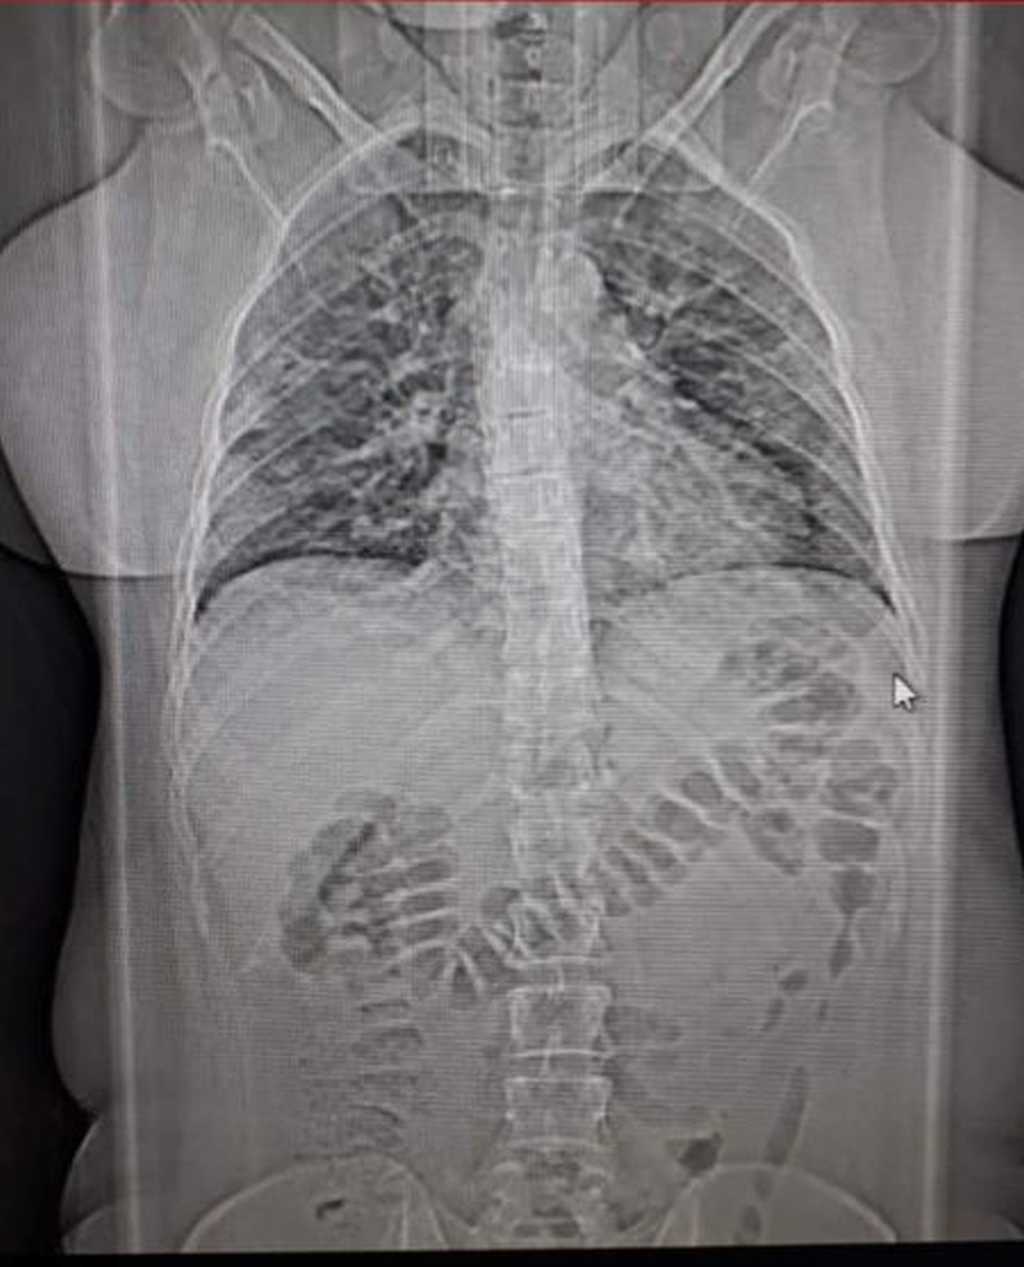

Banho sentado e oxigênio do lado. Dias aterradores, cruéis, impiedosos. Mortes e mais mortes. De pessoas conhecidas, saudáveis até. O surrado “veio a óbito” virou uma espécie de refrão. Doença traiçoeira. Igual cupim. Infestação no assoalho, e logo o forro da casa desaba. Garganta raspando, febre, tosse insistente, pulmões baleados, intestino desanda, enjoo, ausência de apetite, paladar, olfato...

Enfim, a consulta. Suspeita de trombose. A tomografia apontou 60% dos pulmões comprometidos; os exames de sangue revelaram outras mazelas. A ordem era interná-la urgente. Eis a encruzilhada. Hospitais com corredores apinhados. Leitos, nem se cogitava.